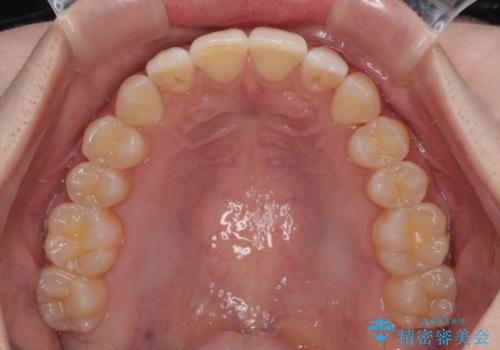

- 上下前歯の重なりを気にして来院された患者様です。

安価なインビザラインパッケージを用いての治療を希望されており、デコボコの程度が中等度であったため、インビザライン・モデレートを用いて矯正治療を行うこととしました。

インビザライン・モデレートは、製作できるアライナーの枚数に制限があるため、移動可能な量に限りがあるものの、インビザライン・ライトよりも枚数が多いため、幅広い症例に対応可能です。